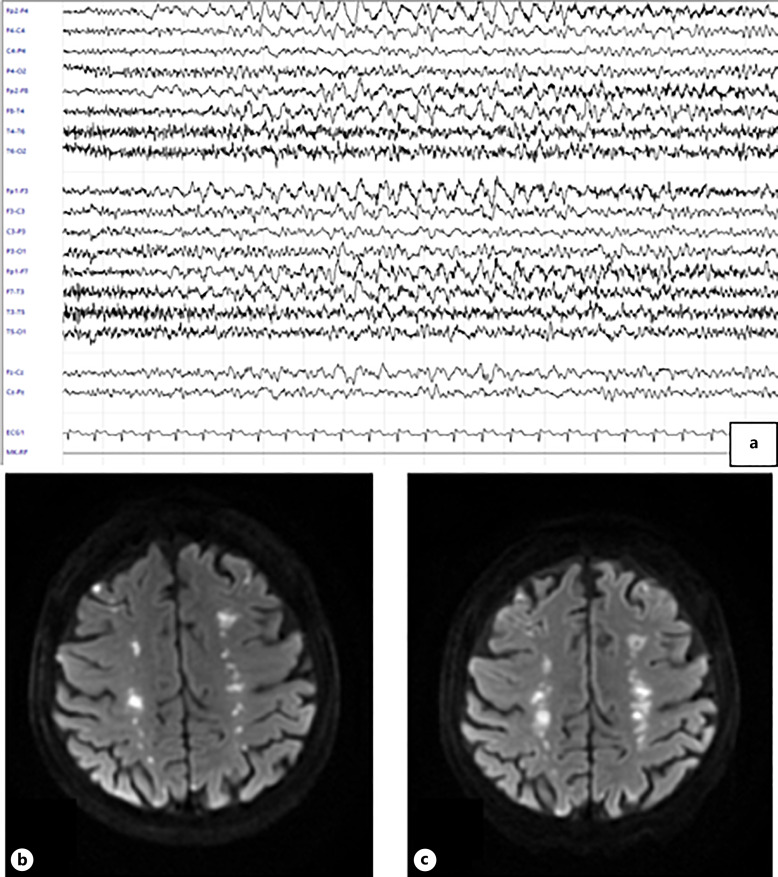

Background: Hypereosinophilic syndrome is characterized by a peripheral blood eosinophil count >1.5 × 103/μL on two different examinations within a month of each other and/or a 20% or higher percentage of eosinophils in a bone marrow section, associated with organ damage. Rarely, neurological manifestations may occur, even in the early stages. We report a case of idiopathic hypereosinophilic syndrome with Loeffler endocarditis presenting with multiple bilateral strokes and encephalopathy as the first clinical manifestations.

Summary: Hypereosinophilia and echocardiographic findings suggested a Loeffler's endocarditis. Blood hyperviscosity and small vessels inflammation induced by the hypereosinophilia itself, the embolization of intracardiac thrombus, along with the impaired clearance of microthrombi in the watershed areas, are the main mechanisms involved in the pathophysiology of stroke in the hypereosinophilic syndrome. Additionally, encephalopathy could be considered as a consequence of multiple cerebral infarcts and neurotoxicity induced by hypereosinophilia since our patient's confusion and aggressive behavior gradually remitted after steroid therapy was started.

Key messages: To the best of our knowledge, our case report is a rare instance highlighting neurological involvement as the earliest manifestation of hypereosinophilia. We aimed to elucidate the central nervous system involvement in this intriguing disorder, with the goal of encouraging clinicians to consider hypereosinophilic syndrome in the diagnostic assessment of rare stroke etiologies.